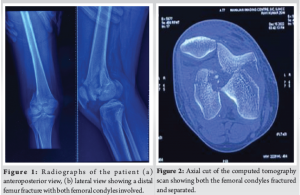

A 25-year-old male presented to the emergency department with a history of a fall from a motorcycle following a road traffic accident. Following initial resuscitation, plain radiographs of the knee were obtained, revealing a distal femur fracture (Fig. 1). Due to the complex nature of the injury and suspected intra-articular involvement, a computed tomography (CT) scan of the knee with 3D reconstruction was performed. It revealed isolated coronal fractures of both femoral condyles, confirming the diagnosis of a double Hoffa fracture (Fig. 2 and 3). Both the fracture fragments were separated, with no bony bridge connecting the two. The fracture was classified as AO 33-B3. After appropriate pre-operative planning and preparation, the patient was taken up for surgery.